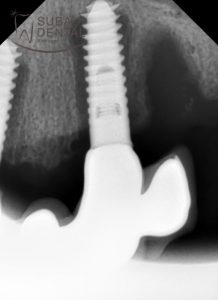

The dark shadow around the implants (peri-implantitis) in the intraoral X-ray scans.